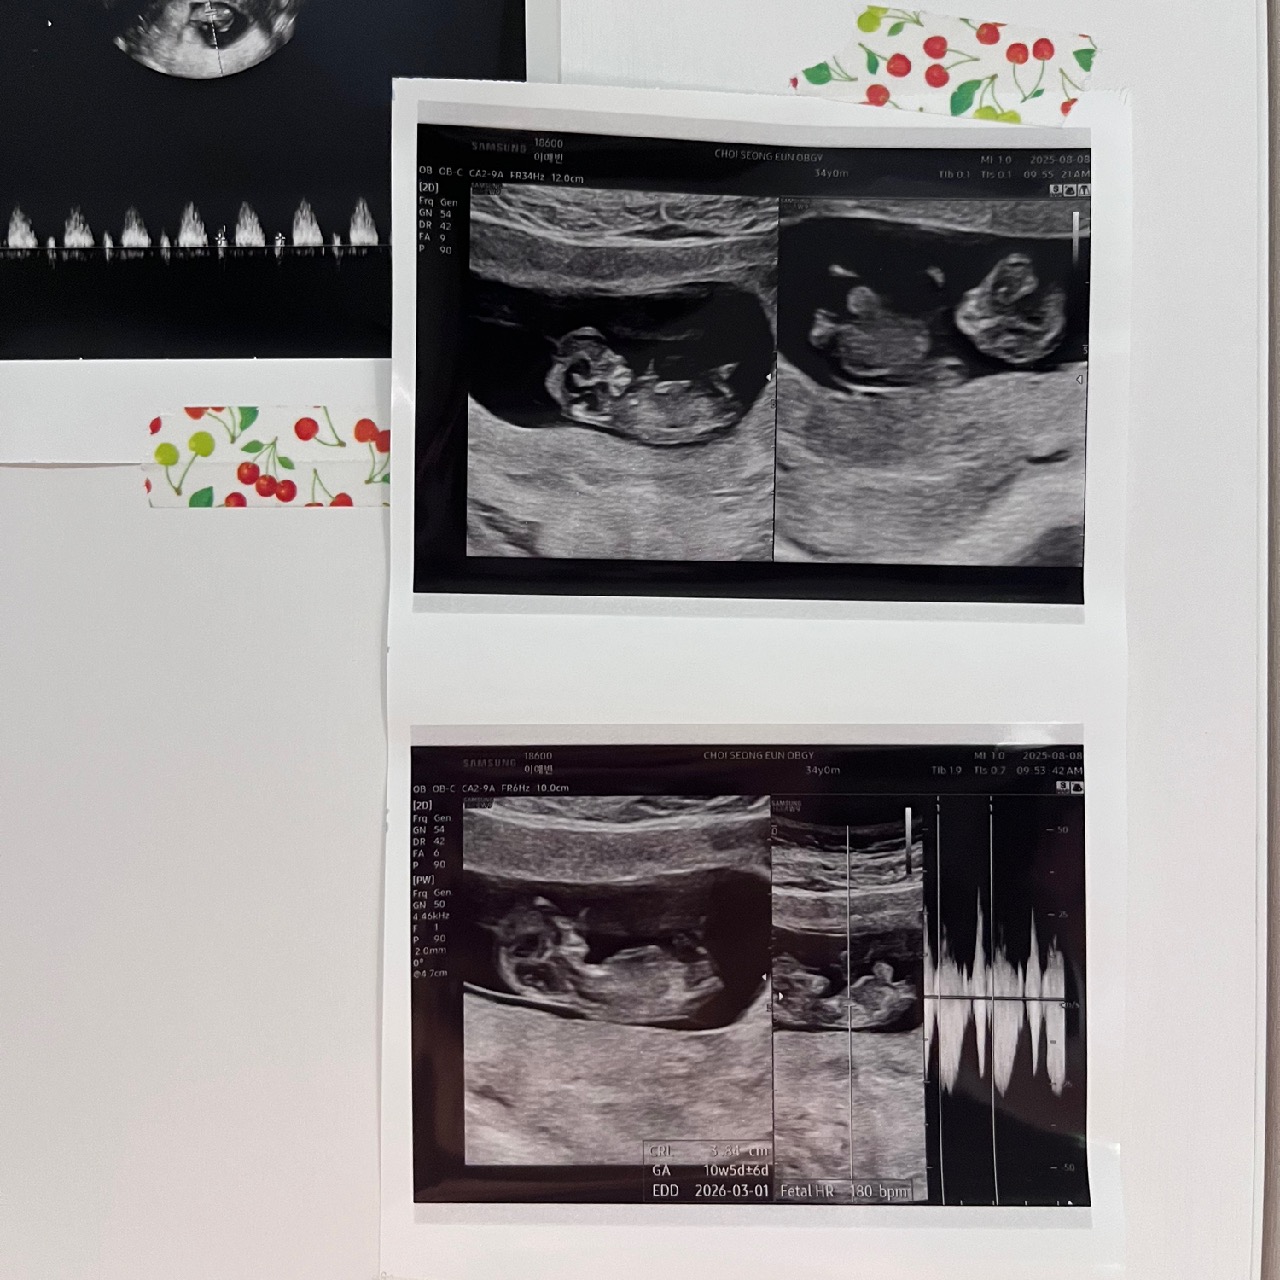

성별맛집.. 최성은 산부인과에 가서 성별 듣고 충격 먹어서 성별 반전 기다리는 나... 확실히 최성은 산부인과가 초음파 화질도 좋고 사진도 예쁘게 잘 찍어 주신다. 내 서브 병원으로 당첨!

우리 완주 🤎 말띠지용~ 초음파 앨범 꾸며야 하는데.. 엄마의 귀차니즘..ㅎ

1차 기형아 검사 때 본 초음파 속 완주. NT 목투명대도 1.3mm로 정상이고~ 엄마 닮아 코뼈를 보니 콧대도 높아 보이고~ 무럭 무럭 잘 크는 일만 남아따!!!!